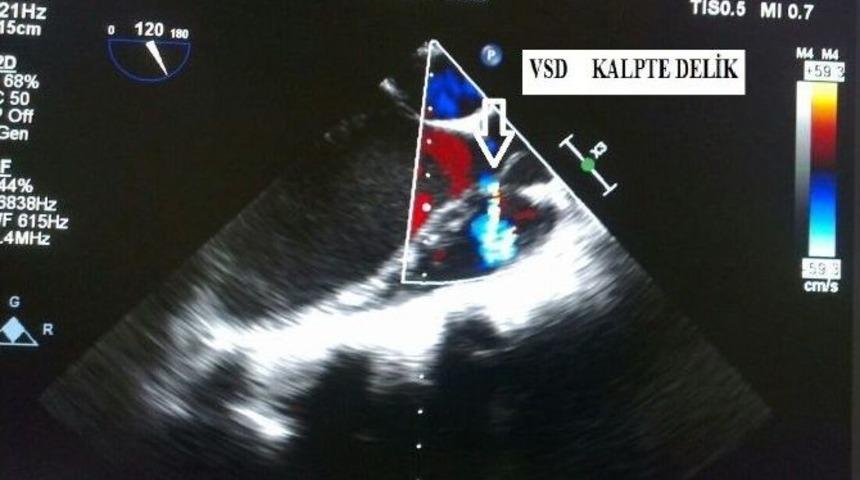

Sakarya Üniversitesi (SAÜ) Tıp Fakültesi Eğitim ve Araştırma Hastanesi Kardiyoloji kliniğinde başarılı bir ameliyat daha gerçekleştirildi.Sakarya Üniversitesi Tıp Fakültesi Eğitim ve Araştırma Hastanesi Kardiyoloji kliniğinde, Tıp Fakültesi Dekanı Prof. Dr. Ramazan Akdemir liderliğindeki ekip, geçtiğimiz günlerde önemli bir ameliyata daha imza attı. Kalbinde delik bulunan 18 yaşındaki bir hasta, yapılan başarılı bir tedavi ile sağlığına kavuştu.Ameliyat hakkında bilgi veren SAÜ Tıp Fakültesi Kardiyoloji Bölüm Başkanı Prof. Dr. Hüseyin Gündüz, “Geçen hafta kalbinde delik olan 18 yaşında bir genç kızımız, başka merkezlerde yapılmaya cesaret edilmediği için ünitemize tedavi amacıyla sevk edildi. Dekanımız Prof. Dr. Ramazan Akdemir liderliğinde bir ekip tarafından, peruktan (kapalı) yolla ameliyatla, yarım saatten kısa süre içinde başarılı bir şekilde tedavisini tamamladık. Hastamızın sağlık durumu şu an gayet iyi ve nefes darlığı, çarpıntı gibi yakınmaları kısa sürede geçti” dedi.Çevre illerden hastaların, tedavi için SAÜ Tıp Fakültesi Kardiyoloji bölümünü tercih ettiklerini dile getiren Prof. Dr. Gündüz, “Dekanımız Prof. Dr. Ramazan Akdemir, Prof. Dr. Ersan Tatlı, Prof. Dr. Harun Kılıç, Doç. Dr. Mehmet Akif Çakar, Doç. Dr. Mustafa Tarık Ağaç, Yrd. Doç. Dr. Mehmet Bülent Vatan kendilerini ispat etmiş değerli ve özel bilim adamları. Bu haliyle üst düzey bir merkeziz, hocalarımız birbirleriyle uyum içinde, destekleyici ve katkı verici şekilde çalışıyor” diye konuştu.Prof. Dr. Gündüz, Sakarya’ya böyle bir klinik kazandırdıkları için çok mutlu ve gururlu olduklarını, bu kliniğe katkılarını esirgemeyen başta rektörümüz Sayın Prof. Dr. Muzaffer Elmas’a, Kamu Hastaneleri genel sekreterimiz Sayın Doç. Dr. Hasan Salih Sağlam’a ve Hastane yöneticimiz Prof. Dr. Zekeriya İlçe’ye çok teşekkür ettiklerini söyledi.